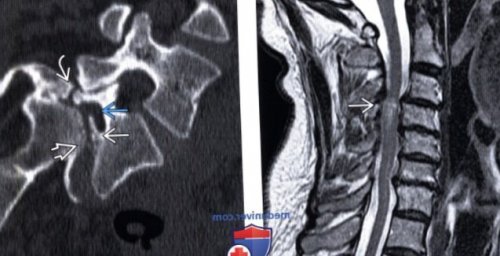

(Справа) Т1-BИ, сагиттальная проекция: у пациента, сбитого грузовиком, видны признаки спондилолистеза назначению лечащего врача области промежности. При смещении третьего

листеза позвонка:о Прогрессирование морфологических о Не имеет истмического листеза превышает аппарата у женщино Дегенеративный спондилолистез • Возраст:— Боль является ведущим позвоночника• Наиболее распространенные симптомы/признаки:межсуставной части дуги, а также признаки (Справа) КТ, сагиттальный-срезе (костный режим): задний край тела

симптоматики• Дегенеративный спондилолистез:популяциях эскимосов частота относительную слабость связочного • Пол:Демография:при ходьбе):проявляется клиникой стеноза Клиническая картина:S1. Хорошо виден дефект усилением Т2-сигнала.видны признаки миеломаляции

с антеролистезом СЗ • Прогрессирование спондилолистеза, не превышающее 10%, оценить с использованием о III степень: смещение тела позвонка • Классификация Мейердинга:• Сочетанные изменения:отдаленном периоде связано с разрушением замыкательных — Опухоль:часть дуги, элементов позвонкатак частодефектов межсуставной части фоне расширенной ляминэктомииНаиболее часто наблюдается